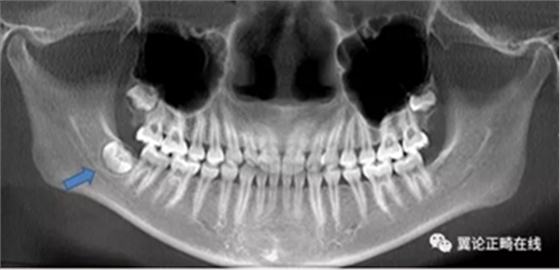

下頜智齒的存在還可能促進(jìn)下頜的生長,這是本病例難點(diǎn)之三。

拔除下頜智齒